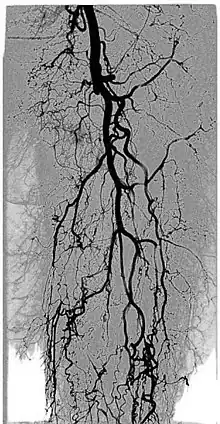

Digital variance angiography (DVA)

See also: Digital variance angiography

The diagnostic value of radiographic images is limited by image quality, which can be measured through signal-to-noise ratio (SNR) calculations. The higher the value of SNR, the better the image. The SNR can be increased initially by enhancing the "signal" or "contrast", which is the intensity difference between the object of interest and the background. This is usually done by adding contrast medium to increase the attenuation values of the object, while holding the background values constant.[1][2][3][4]

By allowing visualization of movements, kinetic imaging offers a new type of motion-based contrast. In many cases, the kinetic image will have a higher SNR (better image quality) compared to traditional images for moving objects.[2][6][1][3][4]

This improvement in SNR and image quality has been studied by Gyánó M. et al. (2018)[3] and Óriás V. et al.(2019)[4] in the field of traditional angiographic imaging and carbon-dioxide imaging. Their findings indicate that by using the kinetic imaging (or as they called this method in the case of angiographies, digital variance angiograpy, DVA) for processing angiographic image sequences, the quality improvement may increase diagnostic insight and it also creates a quality reserve, which means that DVA could provide the same level of image quality, as the gold-standard DSA technique, but the dose of administered radiation and/or contrast agent could be lowered.[3]